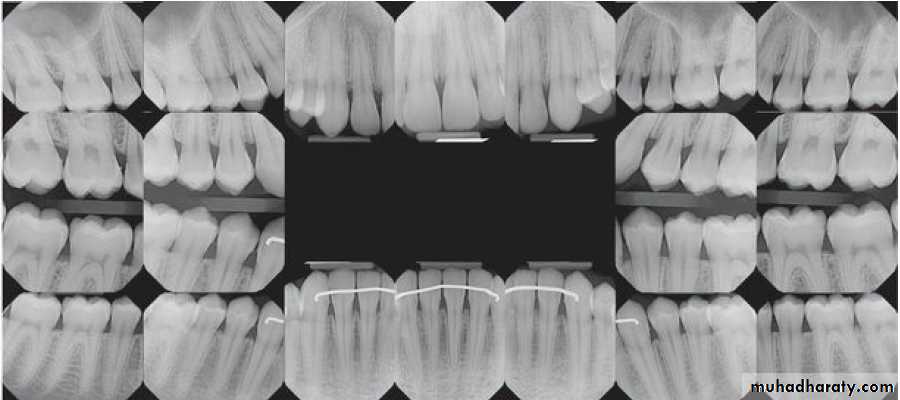

Radiographic Examination:

Radiographs are valuable for the diagnosis of periodontal disease,

estimation of severity, determination of prognosis, and evaluation

of treatment outcome.

The radiographic survey should consist of a minimum of 14

intraoral films and 4 posterior bitewing films.

Panoramic radiographs are a simple and convenient method of

obtaining a survey view of the dental arch and the surrounding

Structures.

The interdental bone normally is outlined by a thin, radiopaque line

adjacent to the periodontal ligament (PDL) and at the alveolar crest,referred to as the lamina dura.

Prichard established the following four criteria to determine

adequate angulation of periapical radiographs:

1. The radiograph should show the tips of molar cusps with

little or none of the occlusal surface showing.

2. Enamel caps and pulp chambers should be distinct.

3. Interproximal spaces should be open.

4. Proximal contacts should not overlap unless teeth

are out of line anatomically.

In conventional radiographs, periapical and bitewing projections

offer the most diagnostic information and are most commonly used

in the evaluation of periodontal disease.